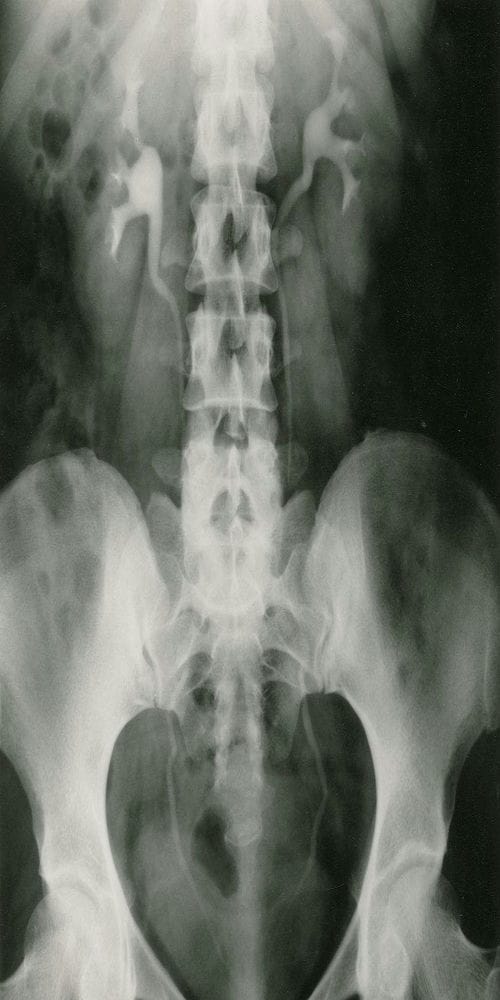

腹部平片:是泌尿系统常用的检查方法; 常规摄取仰卧前后位片。

泌尿系结石:约90%结石可由线平片显示,称为阳性结石;如尿酸盐结石难在平片上显示,称为阴性结石。肾结石可为单侧或双侧性,影像技术中表现为圆形、卵圆形、桑椹状、鹿角状或不定形密度增高阴影;密度可均匀、不均匀或分层状。大多发生在肾盏或肾盂部位,可单发或多发。输尿管结石多由肾结石移行而来,较小的米粒到黄豆大小,大的桑椹或枣核状大小;长轴与输尿管走行一致,常见于生理狭窄处。